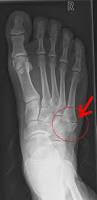

Le 5ème métatarsien est un petit os qui se trouve au bord externe du pied, juste avant le petit orteil. A cet endroit, à la base de l’os s’attache un tendon appelé court péronier ou court fibulaire. Lors de la contraction brutale de ce tendon, par exemple lorsqu’on se foule la cheville – le pied se tourne vers l’intérieur -, la traction de ce tendon sur la base de l’os arrache une petite partie de cette attache.

Une radiographie du pied, généralement de 3/4, permet de savoir s’il y a arrachement osseux en la comparant avec l’autre pied normal. Ce bilan suffit, il est toutefois possible de confirmer le diagnostic avec un scanner voire une IRM (Imagerie par Résonnance Magnétique).